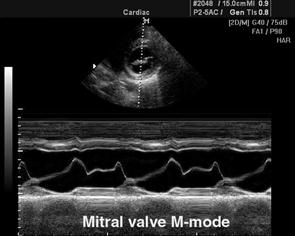

М-метод от­носится к одномерным ульт­развуковым исследованиям (рис. 710250011).

Рис. 710250011. М-метод при исследовании сердца.

М-метод предназна­чен для исследования движу­щегося объекта — сердца. На графике М-разверстки по вертикали откладывается расстояние, по горизонтали - время. В зависимости от положения курсора на экране, можно получить график колебания серии точек, расположенных вдоль курсора, вытянутый во времени, т.е. проследить за их колебанием в систолу и в диастолу.